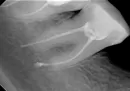

Установили формирователи десны. Чувствую распирание в области имплантов и близлежащих зубов. Мне кажется, что один зуб выдвинулся. И еще у меня произошло не успешное лечение зуба на нижней челюсти.

Возможна ли резекция корня или другая спасительная операция? Может ли нижний 7-й зуб давать такие ощущения на верхнюю челюсть?

Чувство распирания, болезненности, напряженности может возникать от нижнего зуба, но первоначально эти симптомы будут передаваться на сегменты нижней челюсти, а затем уже будут распространяться на верхнюю челюсть. Стоит поискать другую причину, но без клинического осмотра и оценки полноценного рентгеновского снимка судить невозможно. Рекомендуем Вам обратиться к стоматологу-хирургу.